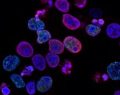

Cáncer

Un tratamiento experimental español acorrala al cáncer: gran eficacia contra el mieloma

Los ensayos han dado un 70% de eficacia contra el mieloma múltiple, uno de los tipos de cáncer más comunes

Los ensayos han dado un 70% de eficacia contra el mieloma múltiple, uno de los tipos de cáncer más comunes -